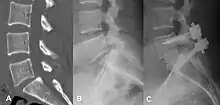

X-ray of the lateral lumbar spine with a grade III anterolisthesis at the L5-S1 level

Classification by degree of the slippage, as measured as percentage of the width of the vertebral body:[14] Grade I spondylolisthesis accounts for approximately 75% of all cases.[6]

• Grade I: 0–25%

• Grade II: 25–50%

• Grade III: 50–75%

• Grade IV: 75–100%

• Grade V: greater than 100%